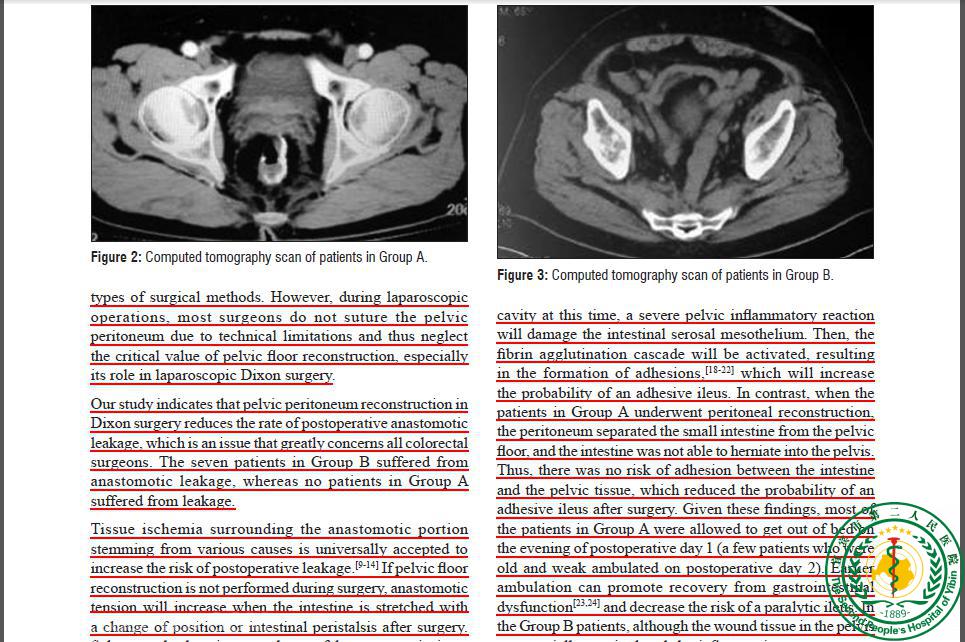

Clinical Significance of Pelvic Peritonization in Laparoscopic Dixon Surgery26283